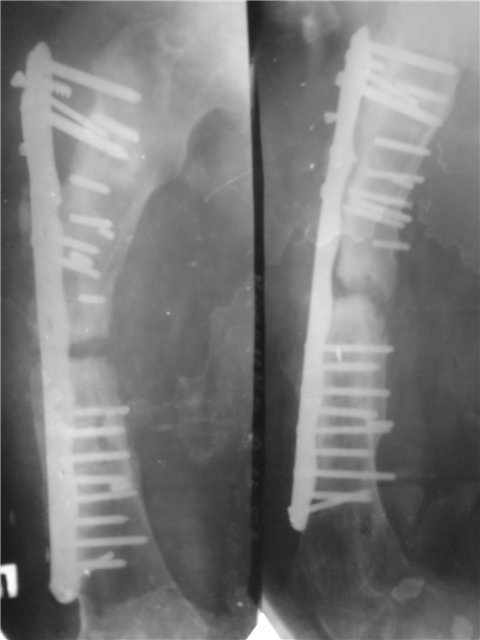

[Ortho] Тактика при ложном суставе бедренной кости

Имя     : 60dabbef0c8b.jpg